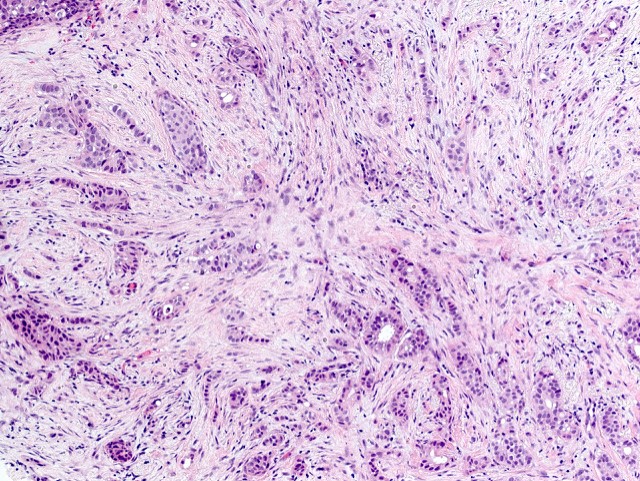

Microscopic (histologic) description

- Histologic grading is based on the Nottingham / modified Bloom & Richardson Score (Histopathology 1991;19:403):

- Histological features of IBC NST vary considerably from case to case and even within the same case

- Margins vary from highly infiltrative, permeating the surrounding tissue, to continuous pushing margins

- Architecture varies from sheets, nests, clusters, cords or individual cells (but lacks the cytomorphological characteristics of invasive lobular carcinoma)

- Tubular formations are prominent in well differentiated tumors but absent in poorly differentiated tumors

- Variable cytological features:

- Cytoplasm may be abundant and eosinophilic but it can show other features in some tumors, including as clear, foamy or granular

- Nuclei may be regular and uniform or highly pleomorphic with prominent or multiple nucleoli

- Mitotic figures are variable from virtually absent to extensive

- 2 distinct growth patterns exist:

- Large and solid nests or syncytial infiltrative growth pattern with little associated stroma and an expansive growth that compresses the surrounding stroma (e.g., most basal-like breast cancers)

- Tumors characterized by small cancer nests accompanied by marked fibrosis (desmoplastic / scirrhous); this type diffusely infiltrates the surrounding tissue as an irregular shaped spiculated mass

- Calcification in 60% of cases, variable necrosis

- Elastosis involves stroma, wall of vessels and ducts and causes grossly noted chalky streaks

- Often ductal carcinoma in situ (DCIS) (up to 80%)

- In some cases, DCIS is extensive

- Associated DCIS is usually of same nuclear grade as the invasive carcinoma

- Perineural invasion (28%)

- Mast cells are associated with low grade tumors

- Uncommon features: eosinophils intraluminal crystalloids (BMC Cancer 2007;7:165, Arch Pathol Lab Med 1997;121:593)

- No myoepithelial cell lining (as seen in DCIS or benign lesions)

- Angiolymphatic invasion in 35%; differs from tissue retraction because:

Microscopic (histologic) images

Contributed by Julie M. Jorns, M.D., Kristen E. Muller, D.O., Gary Tozbikian, M.D. and Emad Rakha, M.D.